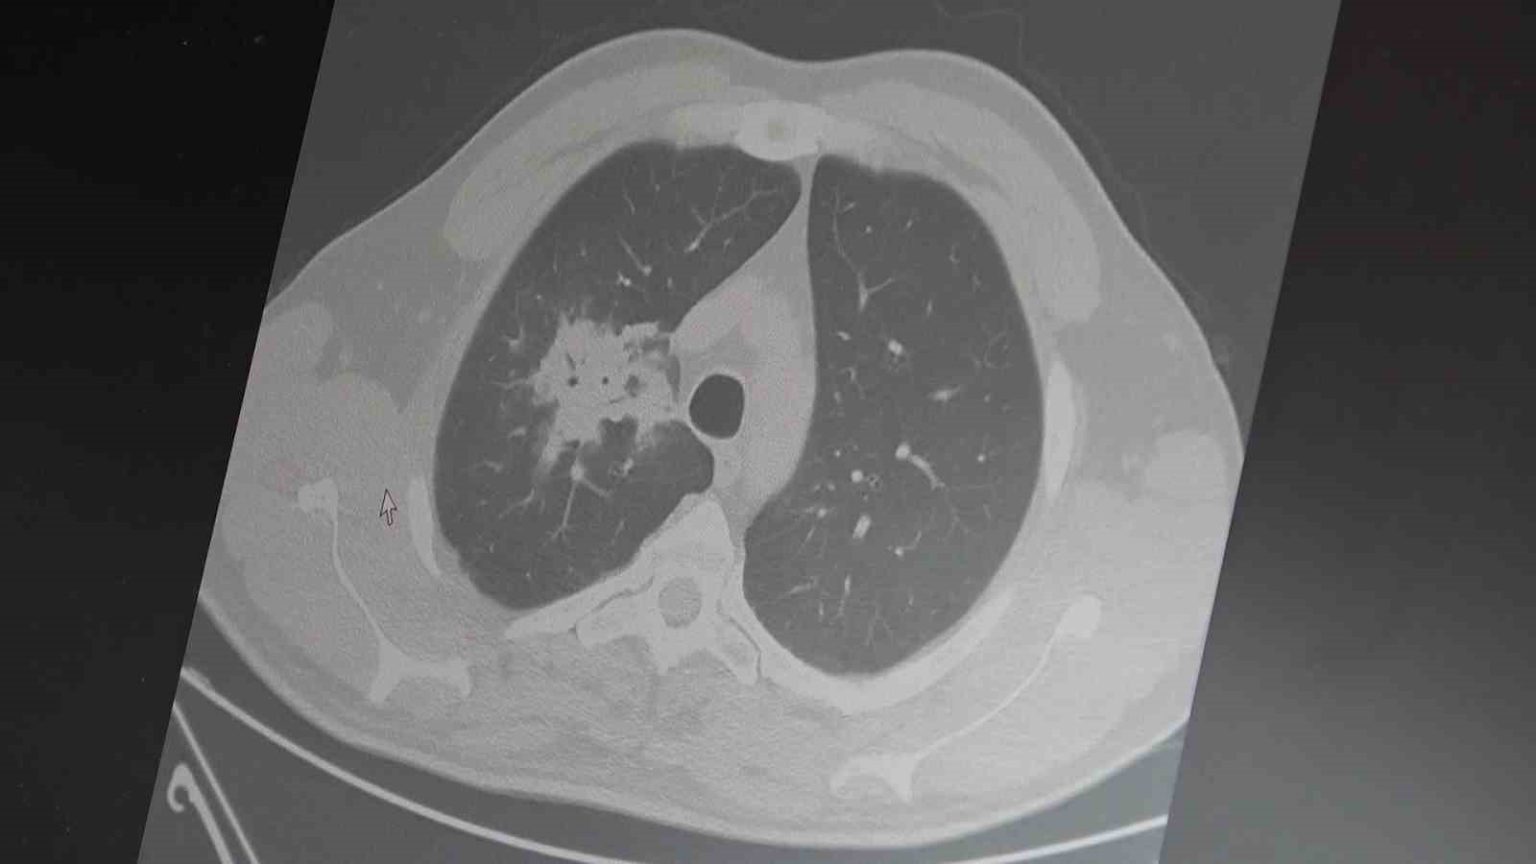

100’den fazla bilimsel çalışmanın incelendiği kapsamlı analizlere dikkat çeken Özkaya, elektronik sigaraların özellikle temas ettiği akciğer ve ağız bölgelerinde kanser riskini artırabileceğine dair güçlü bulgular bulunduğunu belirtti. Uzun vadeli sonuçların henüz tam olarak ortaya çıkmadığını ancak erken uyarı işaretlerinin ciddi olduğunu vurguladı. Araştırmalarda insan, hayvan ve laboratuvar verilerinin birlikte değerlendirildiğini aktaran Özkaya, elektronik sigaraların içerdiği kimyasalların hücre düzeyinde zarara yol açtığının ortaya konulduğunu ifade etti.

2024 yılında yayımlanan bir çalışmaya da değinen Özkaya, hem geleneksel sigara hem de elektronik sigara kullanan bireylerde akciğer kanseri riskinin, sadece sigara içenlere göre dört kat daha fazla olduğunun bildirildiğini kaydetti.